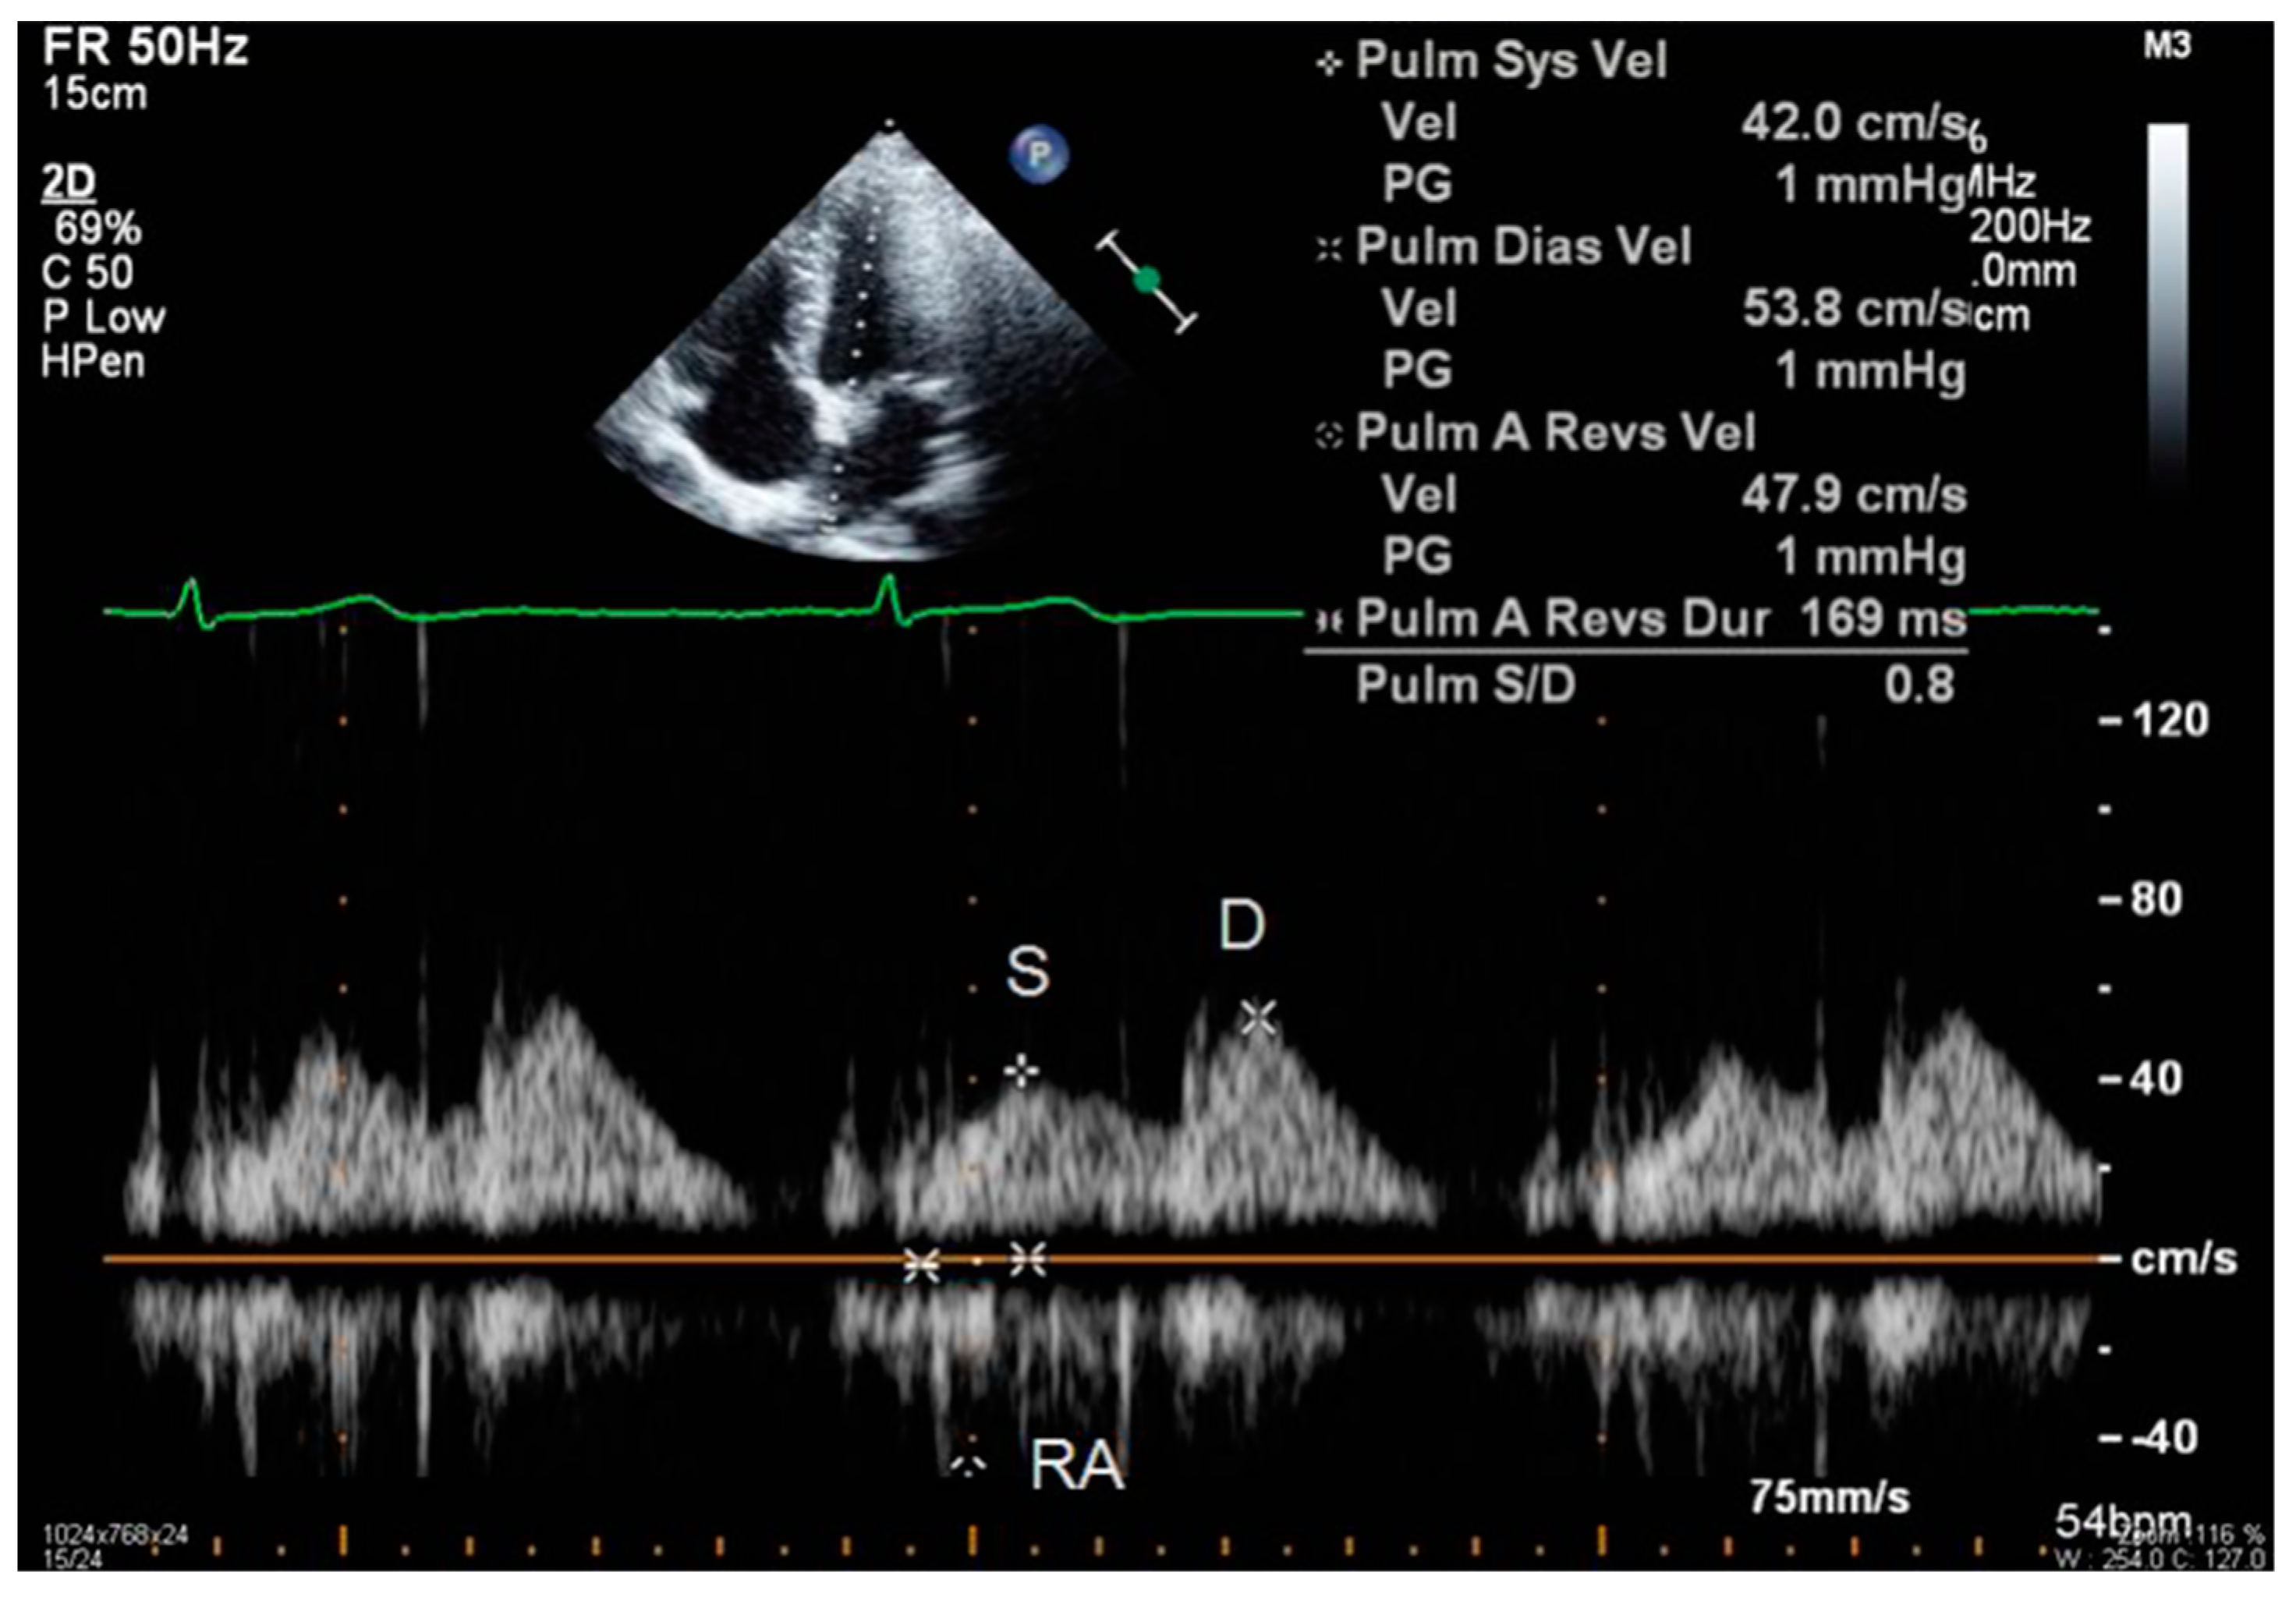

- S and D wave peak velocity on right superior pulmonary vein flow in pulsed Doppler (Figure 6);